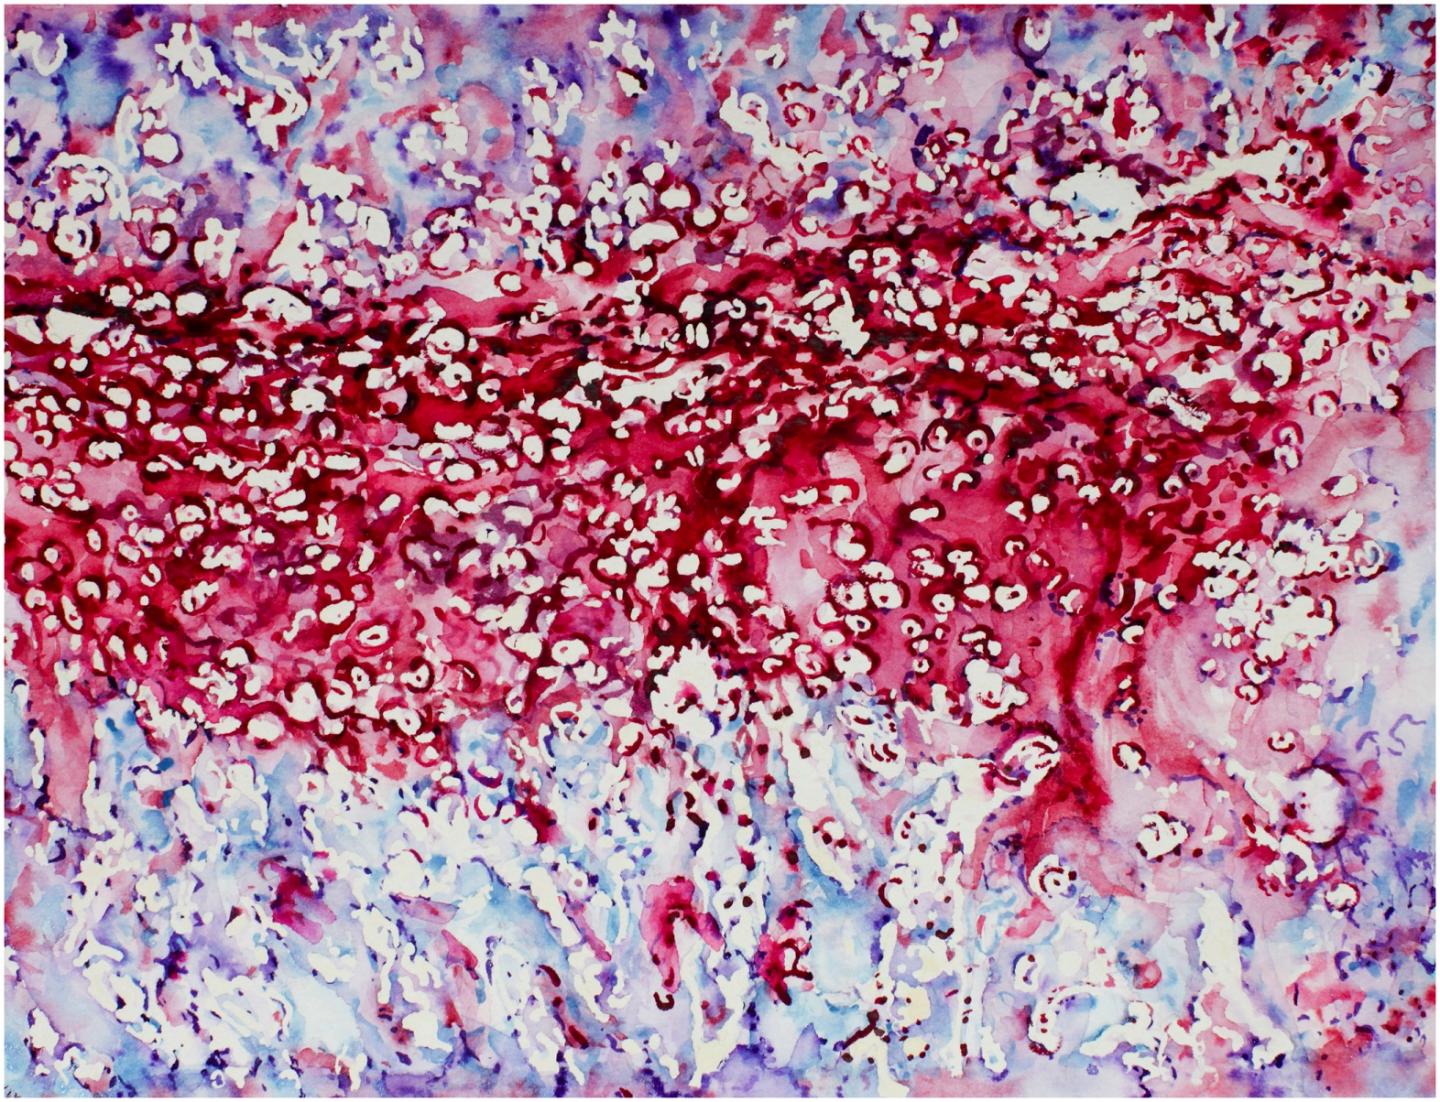

image: A watercolor image depicting the embryonic bone development process, endochondral ossification, featuring cartilage and bone.

"When bones are originally formed in the embryo, they're first generated from cartilage, like a template," said senior author Joel Boerckel, PhD, an assistant professor of Orthopaedic Surgery and Bioengineering at the University of Pennsylvania. "In order to regenerate bone within defects that otherwise won't heal in grown people, we are seeking to recreate the embryonic bone development process."

To do that, the researchers' process begins with the delivery of specially engineered stem cells (called a condensation of mesenchymal cells) to the rodents' bone defect, which sparks endochondral ossification, the specific term for embryonic bone development.